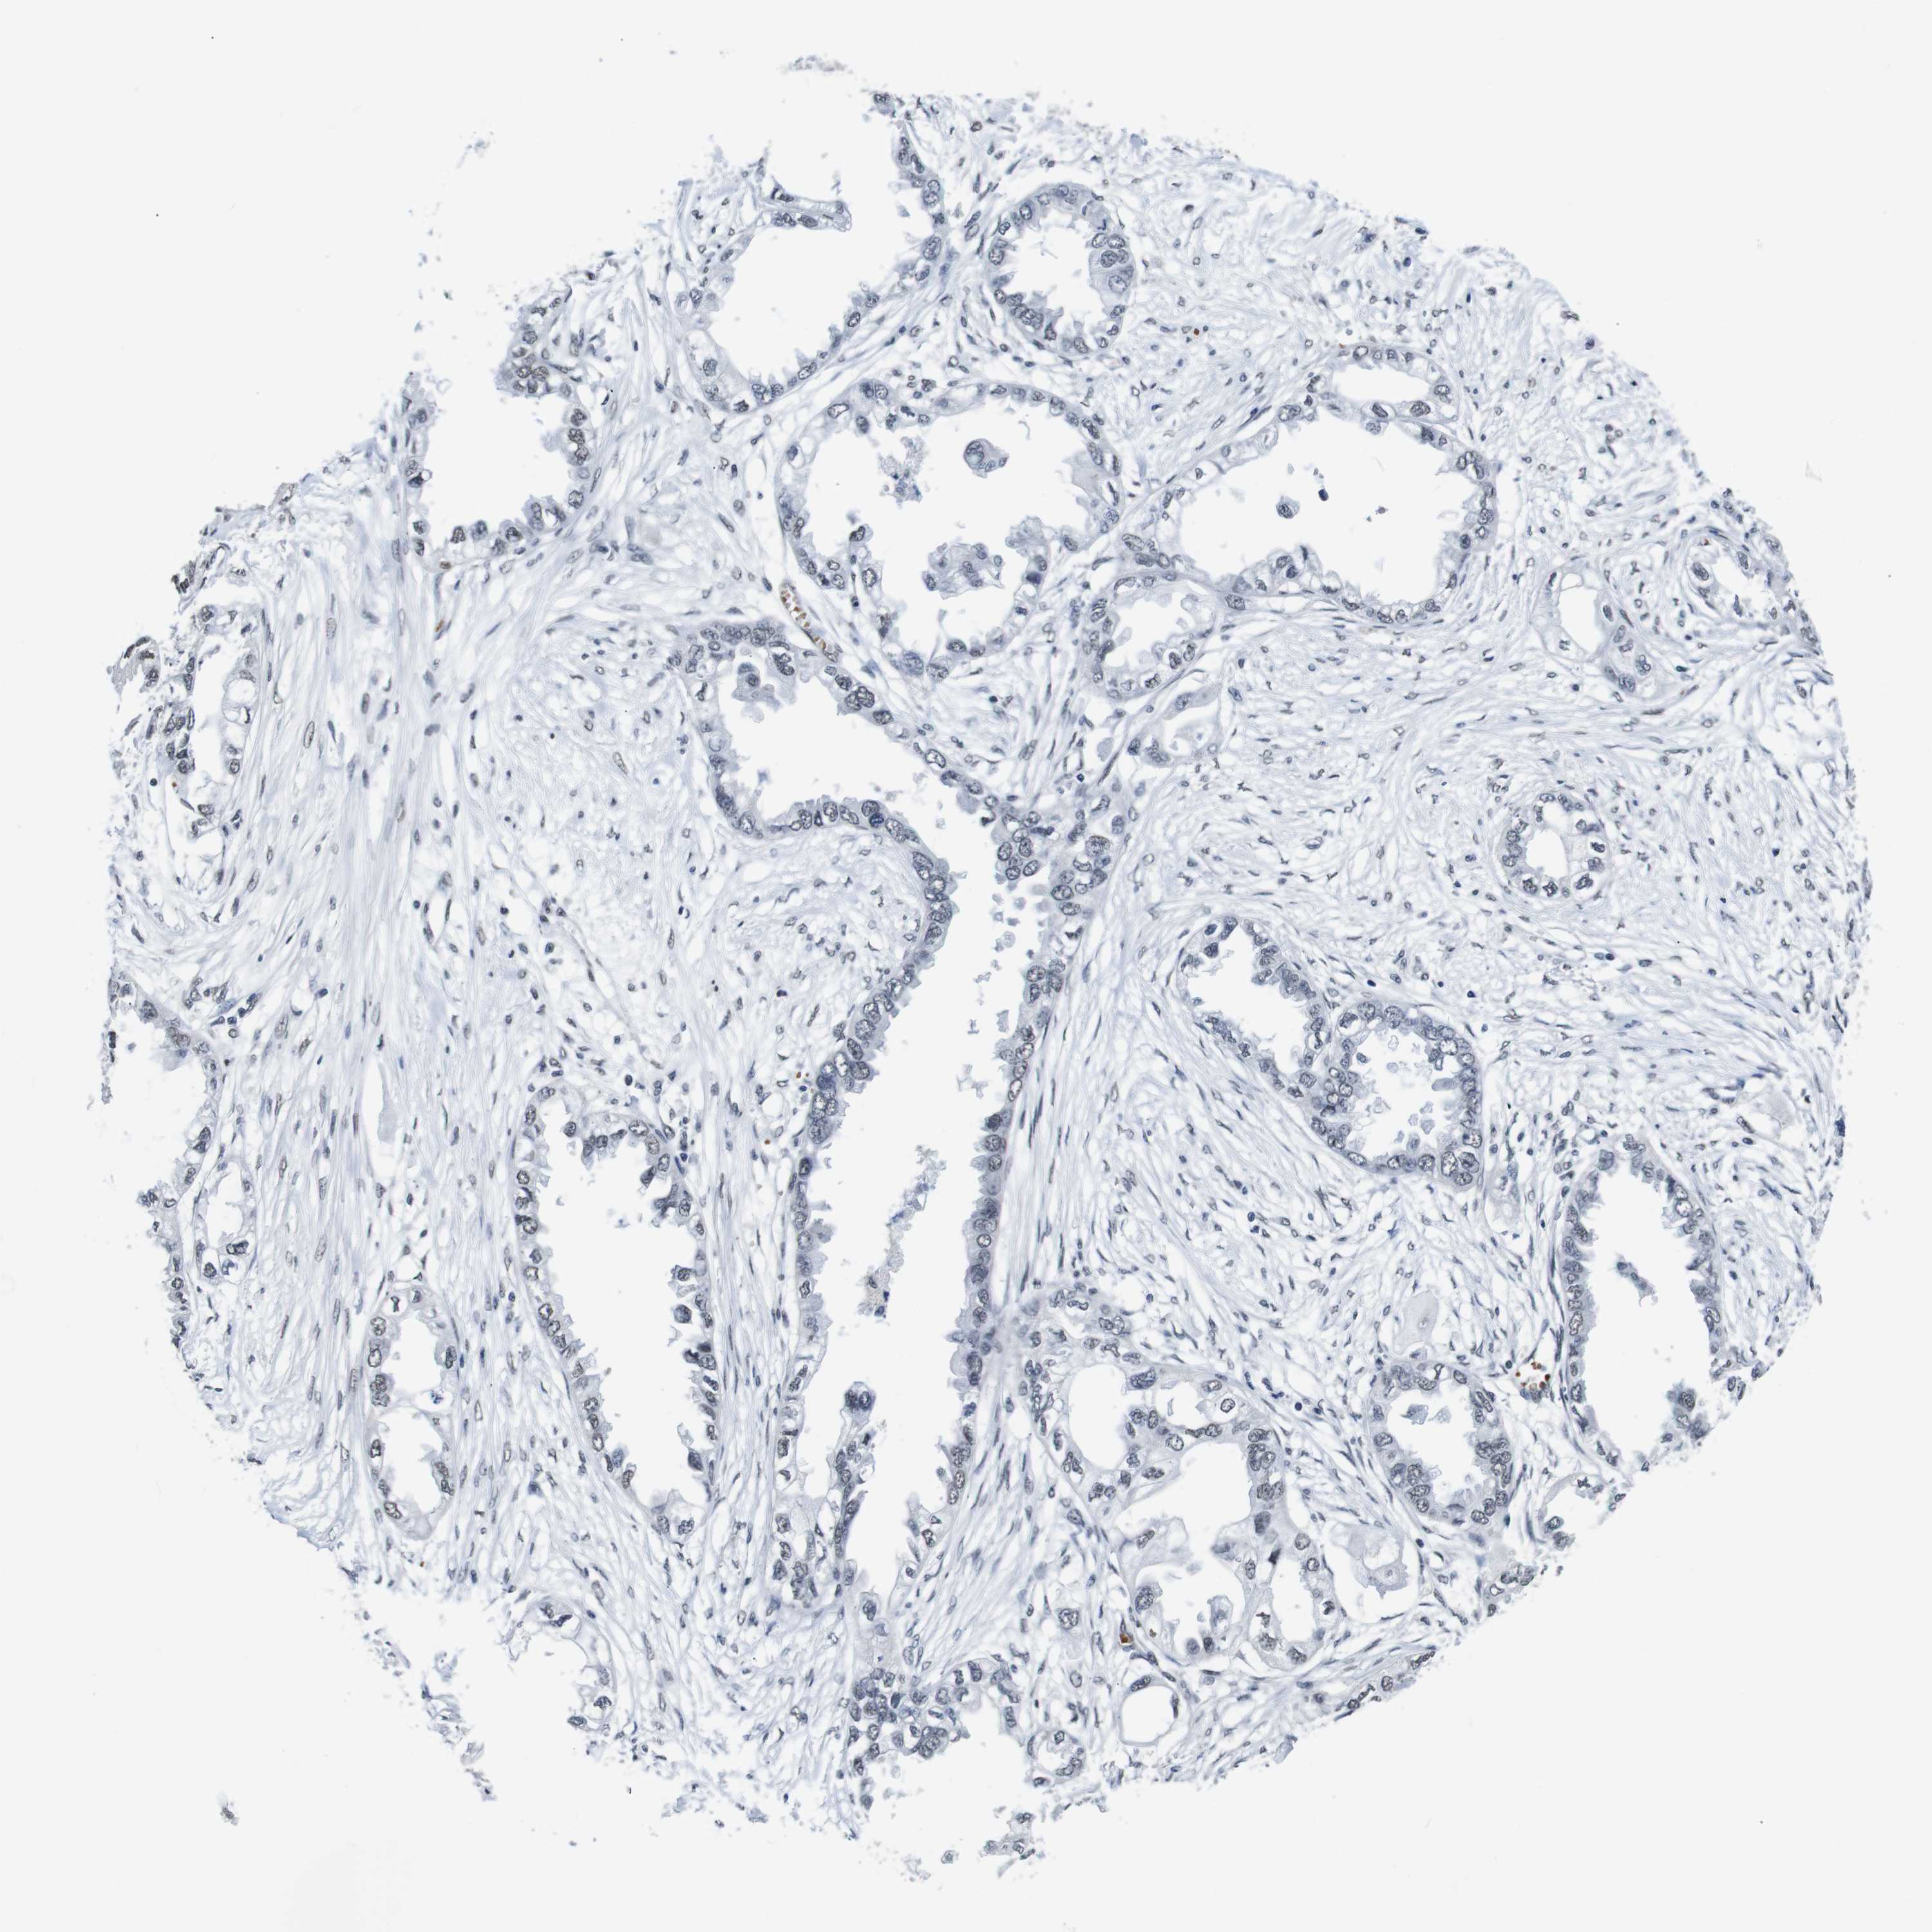

ENDOMETRIAL CANCER - Protein expressioni

A mouse-over function shows sample information and annotation data. Click on an image to view it in a full screen mode. Samples can be filtered based on level of antibody staining by selecting one or several of the following categories: high, medium, low and not detected. The assay and annotation is described here.

Note that samples used for immunohistochemistry by the Human Protein Atlas do not correspond to samples in the TCGA dataset.

Antibody stainingi

Antibody staining in the annotated cell types in the current human tissue is reported as not detected, low, medium, or high, based on conventional immunohistochemistry profiling in selected tissues. This score is based on the combination of the staining intensity and fraction of stained cells.

Each image is clickable and will lead to virtual microscopy that enables deeper exploration of all samples and also displays staining intensity scores, fraction scores and subcellular localization as well as patient and tissue information for each sample.

Antibody HPA012545

Staining

High

Medium

Low

Not detected

Intensity

Strong

Moderate

Weak

Negative

Quantity

>75%

75%-25%

<25%

None

Location

Nuclear

Cytoplasmic/membranous

Cytoplasmic/membranous,nuclear

Adenocarcinoma, NOS

Neoplasm, malignant, NOS